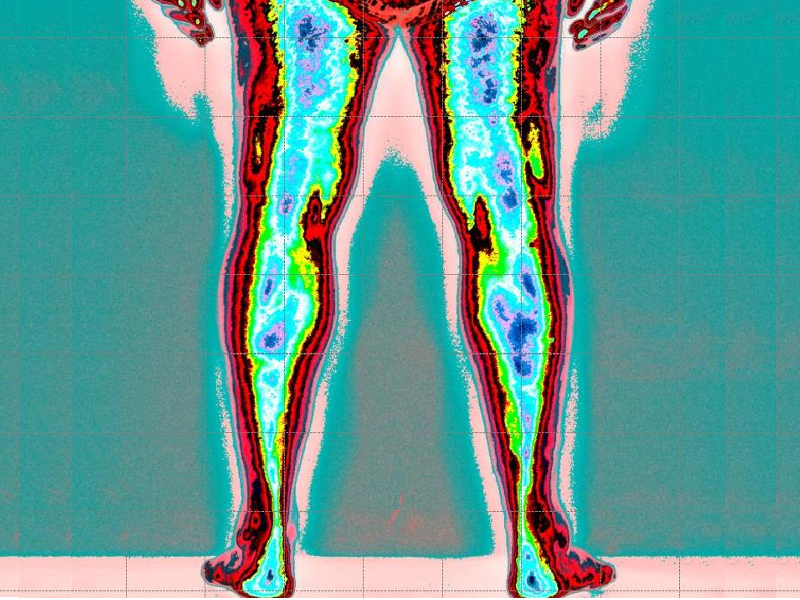

(colore verde azzurro e uniformità nella tensione muscolare)

Dopo il trattamento con Renovatio possiamo notare una normalizzazione della tensione muscolare posturale.

Con conseguente scomparsa delle problematiche di dolore Lombo-sciatalgia

Leggenda: colore rosso inattivazione tensione muscolare

Verde, minima tensione muscolare

Azzurro normale tensione muscolare

Blu scuro, aumento della tensione muscolare